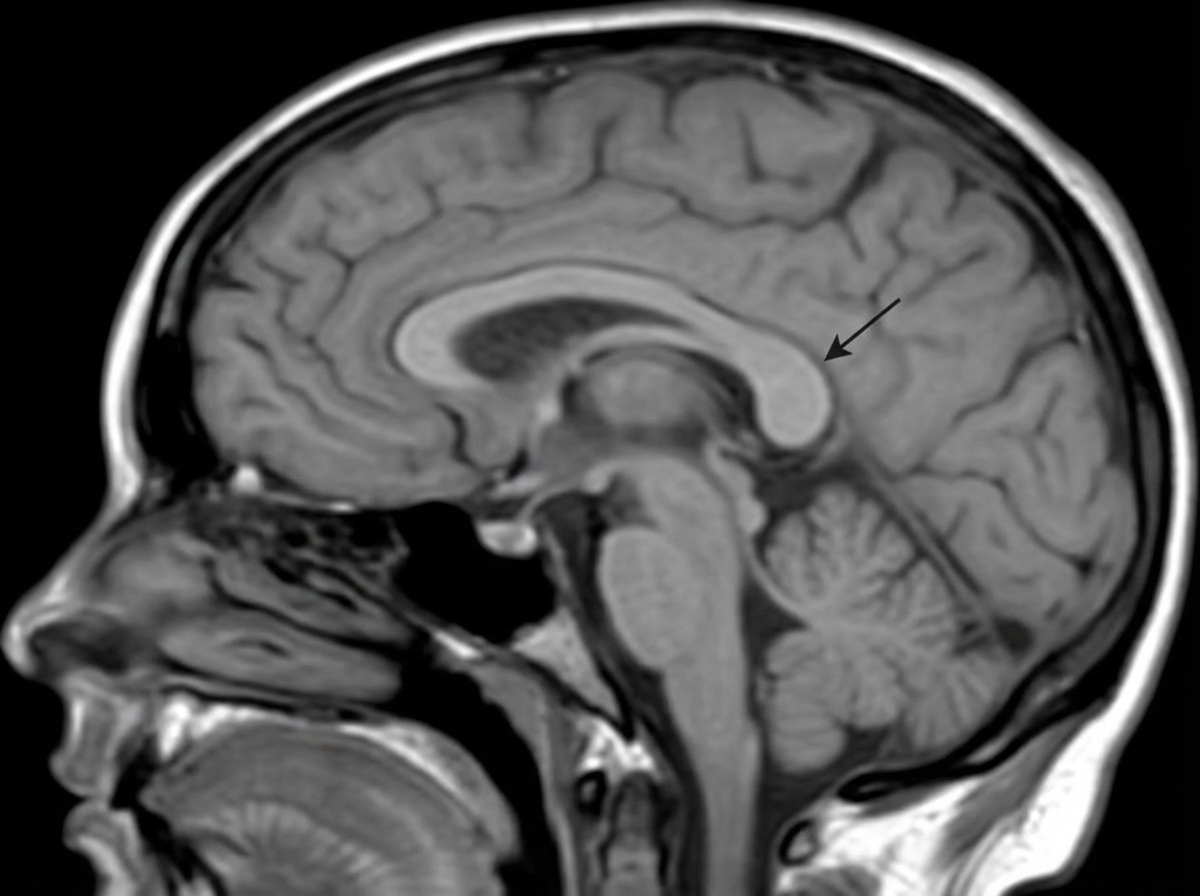

Identify the structure indicated by the arrow in the corpus callosum.

Explanation: ***Splenium*** - The **splenium** is the **posterior thickened rounded end** of the corpus callosum, connecting the **occipital and temporal lobes** of both hemispheres. - It contains **visual association fibers** and is the **most posterior** and **thickest** part of the corpus callosum, making it easily identifiable on sagittal sections. *Rostrum* - The **rostrum** is the **anterior-most thin portion** of the corpus callosum, located **below the genu**. - It connects the **orbital surfaces** of the frontal lobes and is the **smallest** and **thinnest** part of the corpus callosum. *Genu* - The **genu** is the **anterior curved portion** that forms the **knee-shaped bend** of the corpus callosum. - It connects the **prefrontal cortices** and is located **anterior** to the body, not posterior like the structure in question. *Body* - The **body** forms the **main central portion** of the corpus callosum, extending between the genu and splenium. - It has **uniform thickness** and connects the **motor and sensory cortices**, lacking the characteristic **posterior thickening** seen in the splenium.